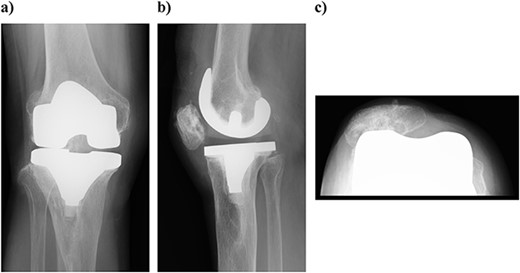

On physical examination, the patient extension and flexion were − 20° and 130°. A defect of the tibial tubercle was observed. The Knee Society (KS) score was 44 points, and the Knee Society function (KS-F) score was 70 points. A plain radiography showed valgus knee osteoarthritis assessed as Kellgren–Lawrence grade 4. In addition, a well-defined translucent image of bone appeared near the central part of the proximal tibia and no tibial tubercle could be observed (Fig. 1). Magnetic resonance imaging (MRI) of the right knee joint showed the patellar tendon appeared from the attachment on the patella with continuity to the tibial bone marrow in T1- and T2-weighted imaging (Fig. 2).

Preoperative simple magnetic resonance imaging: (a) lateral side and (b) axial morphism. T1- and T2-weighted images continuous from the patellar tendon attached to the patella both show continuity from the low signal area to the inside of the tibial bone marrow.